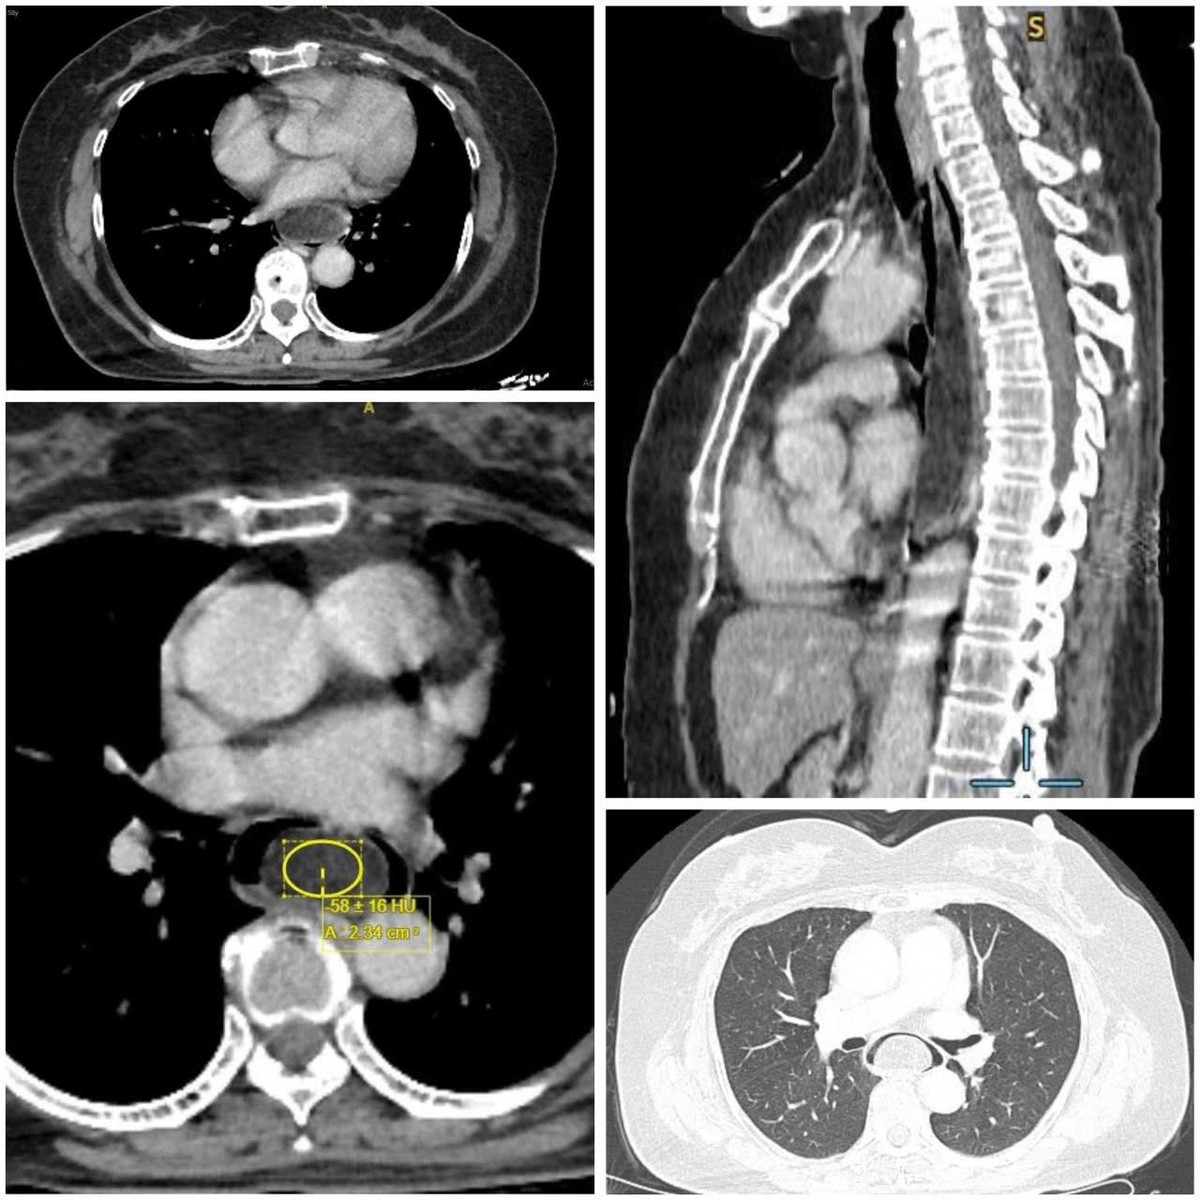

Sau quá trình khám lâm sàng, tìm hiểu diễn biến bệnh, thực hiện nội soi và siêu âm nội soi, các bác sĩ kết luận người bệnh có u mỡ thực quản dưới niêm mạc, kích thước 16 x 3,5 x 3 cm, đây là khối u có kích thước khủng, thông thường các khối u dưới niêm mạc đường tiêu hóa có kích thước thường nhỏ hơn 3cm.

Hình ảnh khu mỡ khủng trong thực quản dưới niêm mạc trên phim chụp - Ảnh BVCC